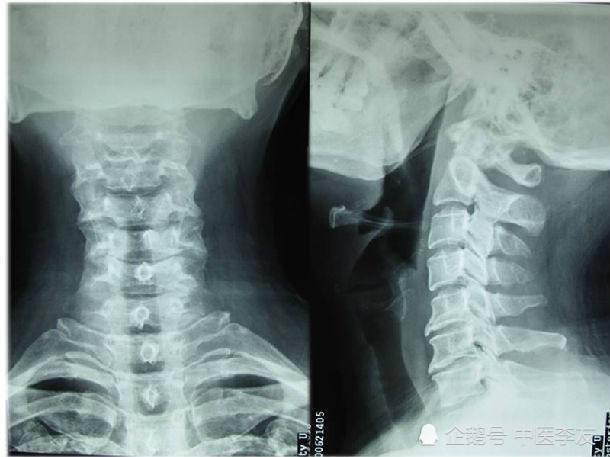

术前dr 颈椎曲度消失,反弓,骨质增生,退变严重.

颈椎骨质增生x光图片

颈椎骨质增生x光片

颈椎骨质增生的图片

颈椎骨质增生影像图

颈椎病骨质增生图片

颈椎骨质增生ct图片